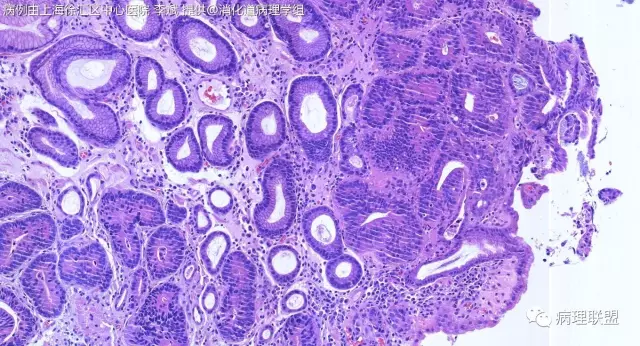

F-56 胃窦粘膜活检(低级别 vs 高级别)

女,56岁,胃窦粘膜活检(病例由上海徐汇区中心医院 李斌 提供,致谢!)

@李斌,高级别,腺体结构乱复杂,核异型性大,极向乱